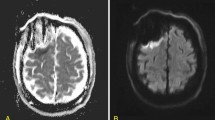

Case 3 (see Fig. 3a)

68-year old female patient (patient #5) with a recurrent right-sided temporal (fusiform gyrus) glioblastoma who underwent re-craniotomy and tumor re-resection. IoMRI showed a total resection and no signs of any DWI restriction. PoMRI, however, depicted a tiny point-shaped DWI lesion with corresponding ADC signal indicating a circumscribed infarct of 0.38 cm3. The patient did not show any new postoperative neurological deficits.

Case 4 (see Fig. 3b)

A 63-year old male patient (patient #8) was operated on an anaplastic astrocytoma WHO grade III in the right temporal lobe, spanning multiple gyri. Since there was no residual tumor seen in ioMRI, no further resection was performed. On the third postoperative day, the MRI showed a clear infarct growth compared to the small band-shaped DWI restriction seen intraoperatively (see Fig. 3b, Table 2). Volumetric analysis showed an infarct volume growth of + 3.6 cm3. Nevertheless, this increased infarct area was not reflected in an impaired neurological status and the patient remained neurologically asymptomatic.